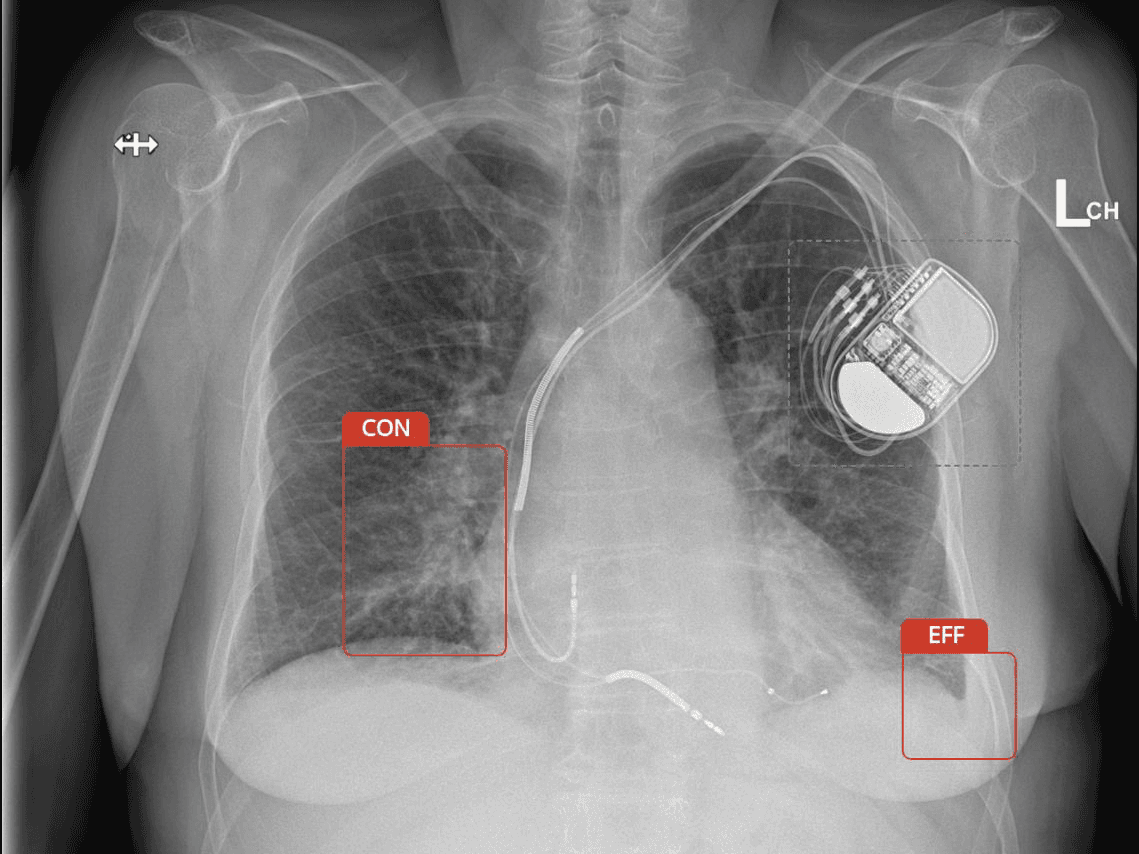

Carebot is a Czech technology startup focused on the use of artificial intelligence in healthcare. Our tool acts as a doctor’s third eye – helping detect findings that might otherwise be missed, accelerating image interpretation, and reducing team workload.

Carebot was created from the belief that technology should support physicians, not burden them. We combined clinical expertise, data science, and artificial intelligence to build a tool that acts as a quiet third eye. It helps detect findings early, speeds up image interpretation, and fits naturally into existing PACS environments without disrupting workflow.